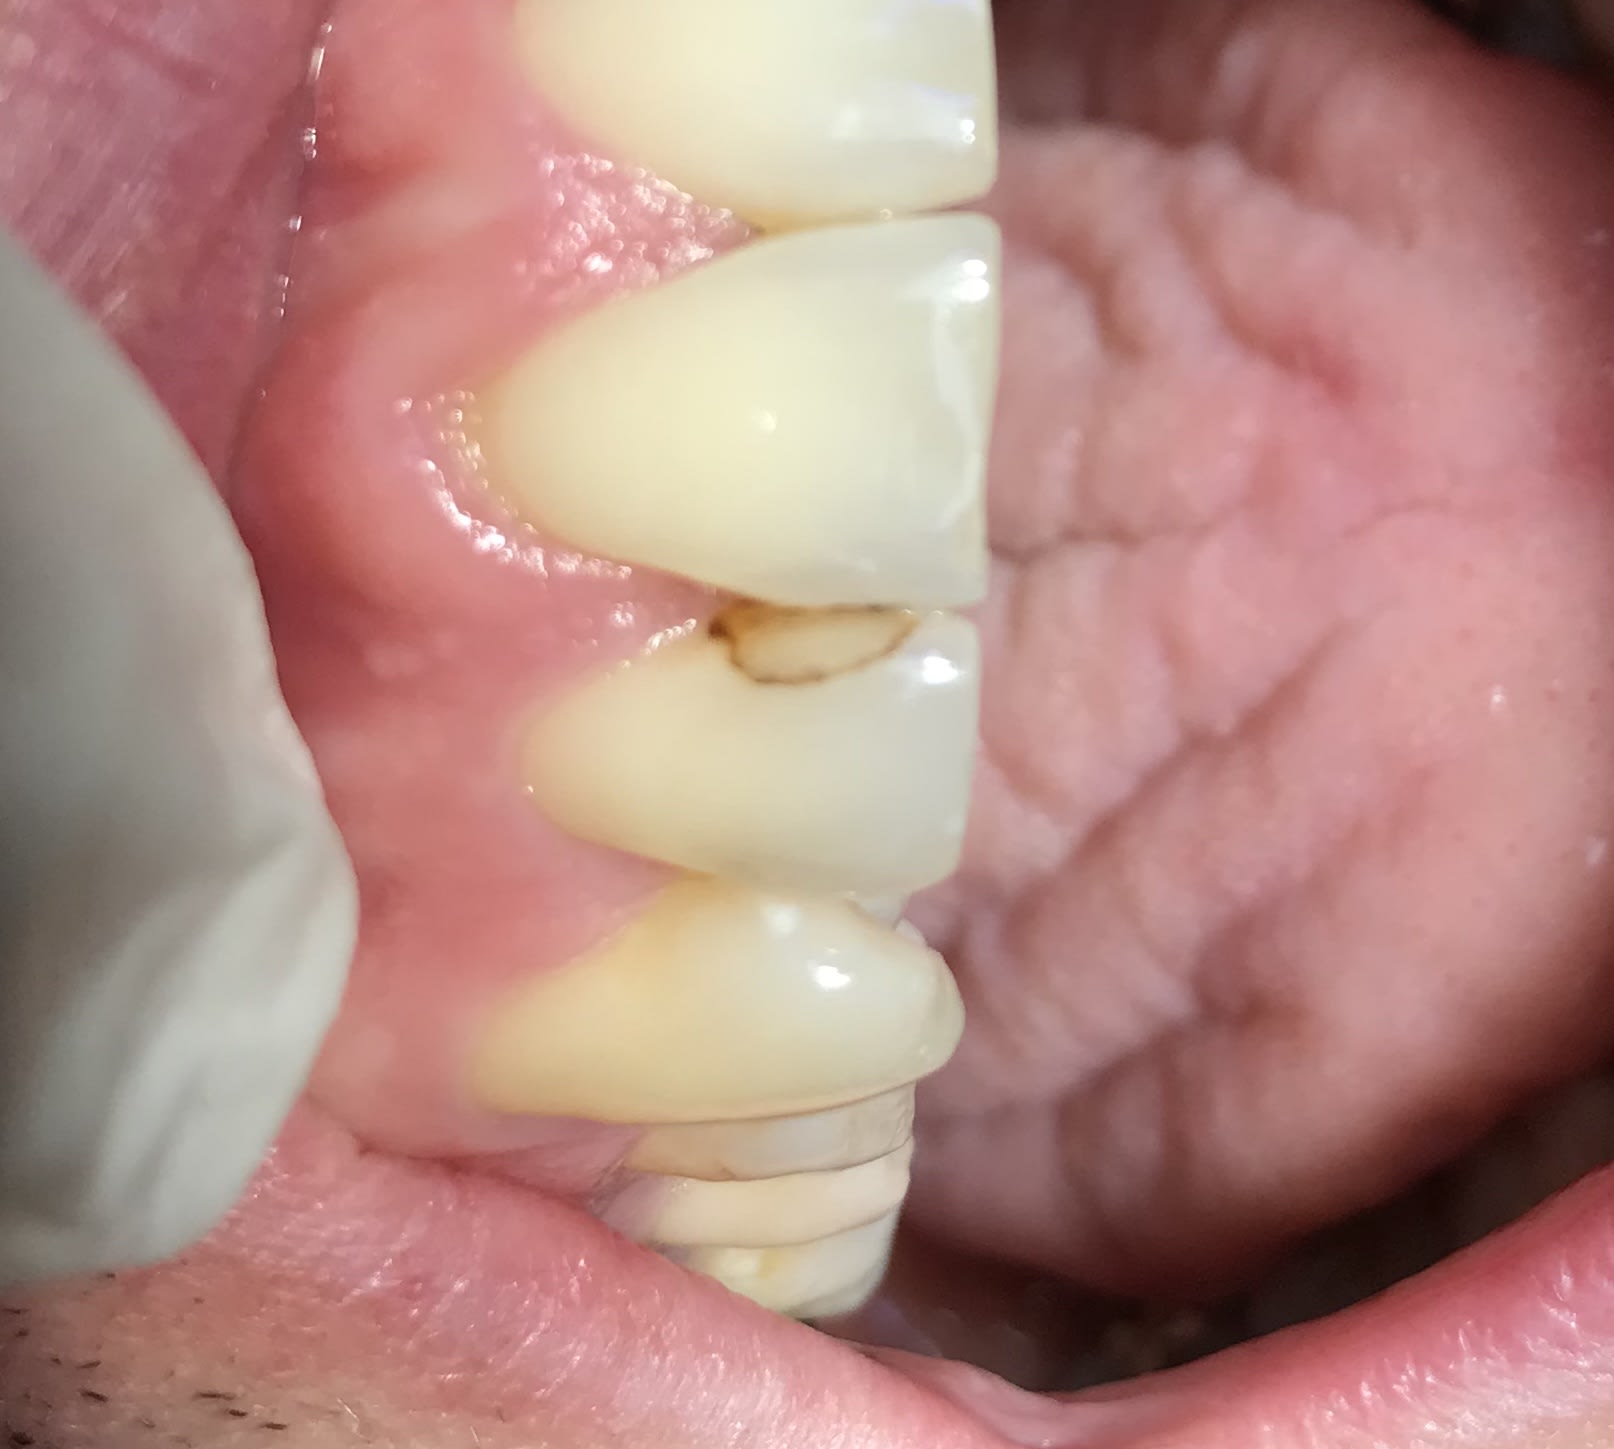

Suis pas certain et échaudé, biopsie.

Paro ras, os ras dents ras. Douloureux, "dur" et peu hémorragique, non sessile, pas trop mobile.

Dscf3073 2 iixu45 - Eugenol

Dscf3075 blndsy - Eugenol